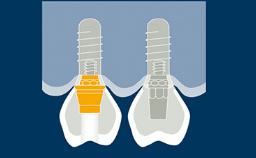

Prosthodontic Planning and Procedures

Abutment Selection for Fixed Dental Prostheses

Learning Module